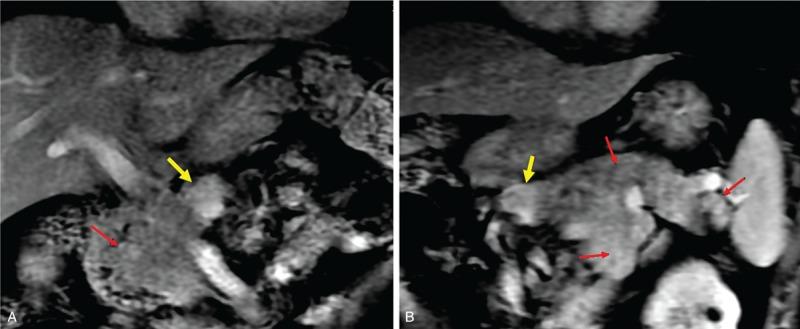

Intraoperative localization and confirmation of complete resection of the hypersecreting tissue are the 2 main challenges in the management of pancreatogenous hypoglycemia. Here, we report our experience with intraoperative portal vein insulin assay combined with occlusion of the pancreas in the management of pancreatogenous hypoglycemia. Clinical courses of 2 patients with biochemical evidence of a pancreatogenous hypoglycemia were studied. The preoperative diagnosis was multiple endocrine neoplasia 1 (MEN-1) and nesidioblastosis, respectively. Rapid intraoperative portal vein insulin assay combined with occlusion of the pancreas was used to localize and confirm complete excision of the hypersecreting tissue. Hypoglycemia was successfully treated in both the patients. In the MEN-1 patient, 2 small tumors in the head of pancreas were not resected, as they were deemed noninsulin secreting by intraoperative portal vein insulin assay, thus avoiding a total pancreatectomy. In the patient with nesidioblastosis, using intraoperative portal vein insulin assay combined with occlusion of the pancreas, an appropriate amount of pancreatic tissue was resected thereby avoiding recurrence and diabetes. This technique may be of particular value in patients with complex conditions such as MEN-1 and nesidioblastosis, to localize and achieve complete resection of hypersecreting pancreatic tissue.

术中定位并确认高分泌组织的完全切除是胰源性低血糖症治疗中的两大主要挑战。在此,我们报告我们在胰源性低血糖症治疗中联合胰腺阻断进行术中门静脉胰岛素测定的经验。研究了2例有胰源性低血糖生化证据患者的临床病程。术前诊断分别为多发性内分泌腺瘤1型(MEN-1)和胰岛细胞增殖症。术中快速门静脉胰岛素测定联合胰腺阻断用于定位并确认高分泌组织的完全切除。两名患者的低血糖症均得到成功治疗。在MEN-1患者中,胰腺头部的2个小肿瘤未被切除,因为术中门静脉胰岛素测定认为它们不分泌胰岛素,从而避免了全胰切除术。在胰岛细胞增殖症患者中,通过术中门静脉胰岛素测定联合胰腺阻断,切除了适量的胰腺组织,从而避免了复发和糖尿病。这项技术在诸如MEN-1和胰岛细胞增殖症等复杂病情的患者中,对于定位并实现高分泌胰腺组织的完全切除可能具有特殊价值。